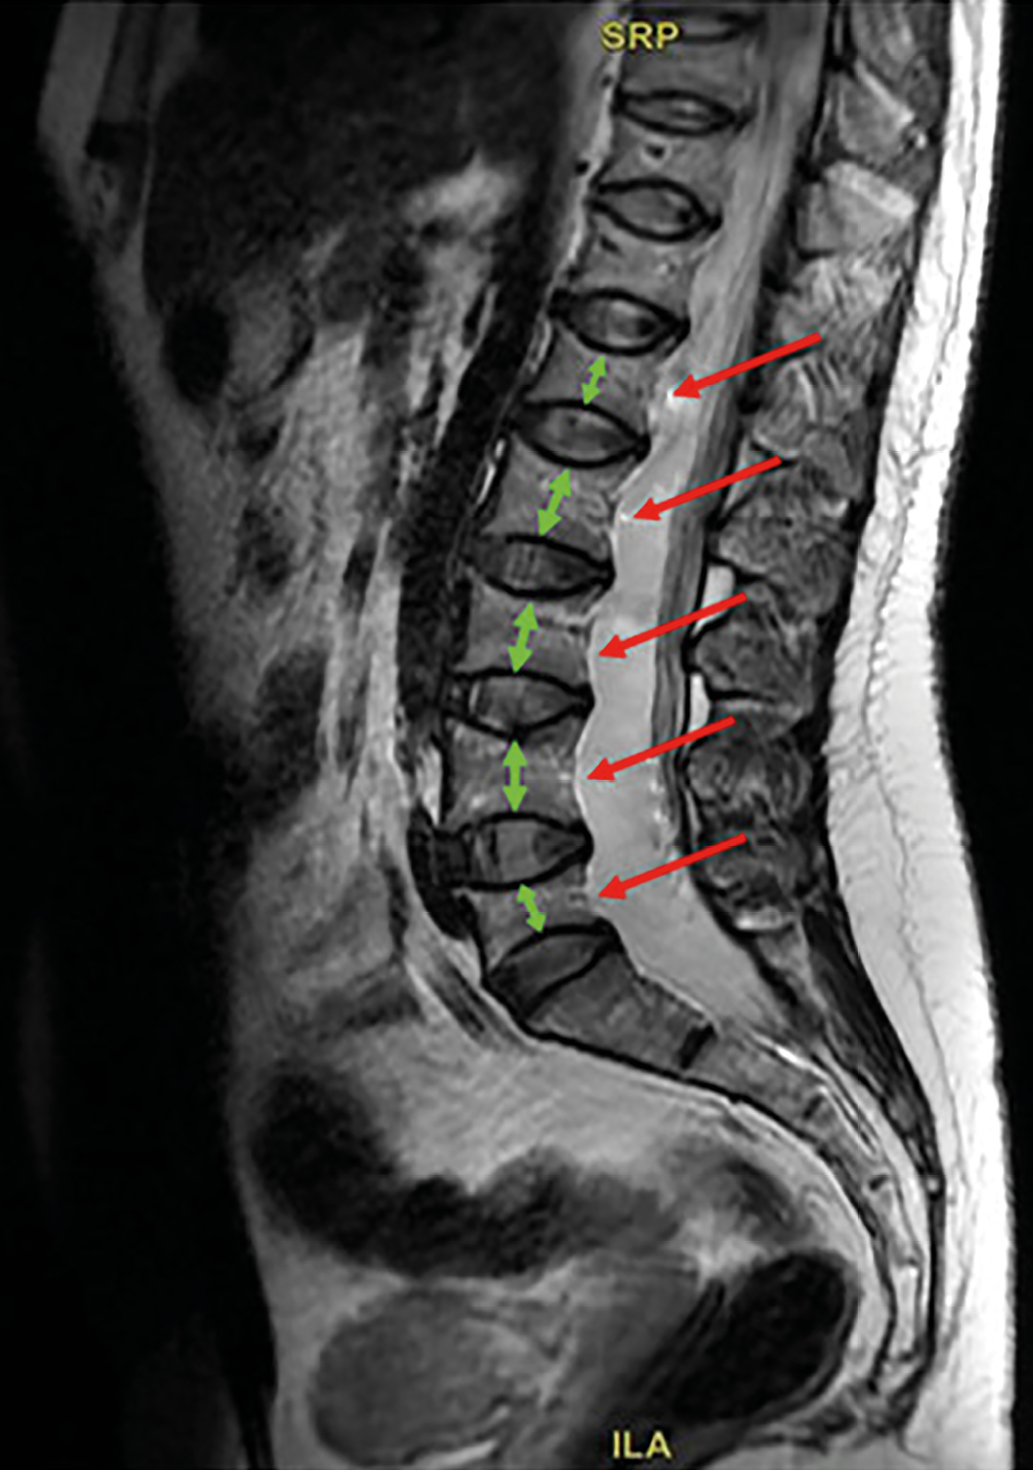

Рисунок 2. Магнитно-резонансная томография поясничного отдела позвоночника пациентки Б.

Режим Т2-ВИ. Сагиттальный срез.

Определяется двояковогнутая деформация замыкательных пластин тел L1–L5 позвонков с формированием деформации по типу «рыбьих» позвонков. Высота тел позвонков снижена, форма тел позвонков напоминает двояковогнутую линзу. Описанные изменения наиболее выражены на уровне L1 и L5 позвонков, где степень снижения высоты достигает 43 и 54%, соответственно.

Figure 2. MRI of the lumbar spine of patient B.

T2-WI. Sagittal view.

The following is observed: Biconcave deformation of the endplates in the vertebral bodies of L1–L5, resulting in «fish vertebrae» deformities. The vertebral body height is reduced, and their shape resembles a biconcave lens. These changes are most pronounced at the L1 and L5 levels, where the degree of height reduction reaches 43% and 54%, respectively.

Основные рентгенологические признаки остеомаляции включают структурные изменения костной ткани, проявляющиеся в генерализованном снижении ее видимой плотности, деформации позвонков и характерных псевдопереломах — зонах Лоозера. Последние представляют собой просветления шириной 2–5 мм, перпендикулярные длинной оси кости или надкостницы и ограниченные склеротическими краями — синдром Милкмана [22]. На МРТ-снимках симметричная двояковогнутость («рыбьи позвонки») формируется вследствие прогиба мягкой позвоночной кости под давлением межпозвоночных дисков. Эти изменения служат ключевым диагностическим признаком остеомаляции и резко контрастируют с переднеклиновидными компрессионными переломами тел позвонков, типичными для остеопороза [23].

DXA не позволяет достоверно оценить степень нарушения минерализации костной ткани, что требует применения дополнительных методов диагностики. Отсутствие компрессионных переломов, характерных для остеопороза, и наличие двояковогнутых деформаций тел позвонков на МРТ («рыбьи позвонки») служат важным диагностическим критерием остеомаляции. Дополнительным фактором, опровергающим диагноз ОБЛ, является продолжающееся у пациентки прогрессирование болевого синдрома, несмотря на прирост МПК на фоне применения антирезорбтивной терапии.